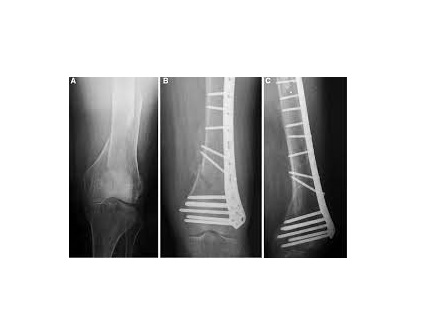

Minimally Invasive Fracture / Trauma Surgery Minimally invasive surgery has achieved fame for certain operations in general surgery over the last two decades, as the reduction in surgical insult has produced faster recovery with enhanced patient satisfaction and favorable health economics. Implants and surgical techniques for minimally invasive osteosynthesis in periarticular, spinal and pelvic fractures underwent rapid improvement. They show adequate healing along with low complication rates and satisfactory outcome. Computer-assisted insertion of implants and navigation offer new possibilities and are particularly advantageous in difficult anatomical regions, such as the pelvis or spine. The treatment purpose in minimally invasive orthopedic surgery consists of anatomic reconstruction and stabilization of the articular surface, length, axis and rotation with minimal soft-tissue trauma. Recent advances in techniques and technology implementing minimally invasive approaches as the gold standard of treatment in the near future. To know more book an appointment on www.drrohanbhiwgade.com orthopedic surgeon in Vashi | orthopedic doctor in Vashi | Fracture specialist in Vashi